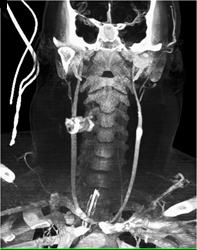

Carotid Artery Stenosis